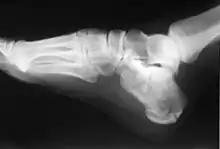

العَقِبِيّ[2] أو العَظْم العَقِبِيّ أو عَظْم العَقِب[2] (بالإنجليزية: Calcaneus) [ملاحظة 1] هو أكبر عظام الرُصُغ يقع في القسم الخلفي من القدم، ويطلق عليه أيضاً عظم الكعب حيث أنه العظم من طرسوس في القدم والتي تشكل الكعب. في بعض الحيوانات الأخرى، هو نقطة العرقوب.

يعد عظم العقب أكبر عظام الرصغ. يتمفصل في الأعلى مع عظم القعب ويتمفصل في الأمام مع العظم النردي، وله ستة وجوه:

• الوجه الأمامي: يتمفصل مع العظم النردي.

• الوجه الخلفي: يتميز بوجود البارزة الخلفية للقدم التي يرتكز عليها وتر العقب.

• الوجه الوحشي: يوجد عليه بروز يُسمى الحدبة الشظوية التي يرتكز عليها وترا العضلة الشظوية القصيرة والعضلة الشظوية الطويلة.

• الوجه الأنسي: يبرز منه ناتئ له شكل الرف يُدعى بمعلاق القعب لأنه يساهم في دعم عظم القعب.

• الوجه العلوي: يتميز بوجود سطحين مفصليين يتمفصل عظم العقب من خلالها مع عظم القعب وينفصلان عن بعضهما بالثلم العقبي.

• الوجه السفلي: يتميز بوجود ثلاث حدبات، حدبة أمامية وحدبة أنسية كبيرة وحدبة وحشية صغيرة.